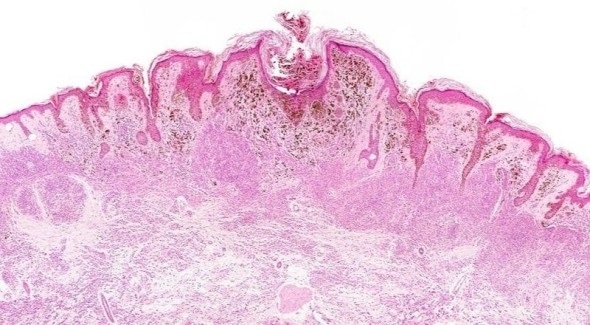

Credit: iStock